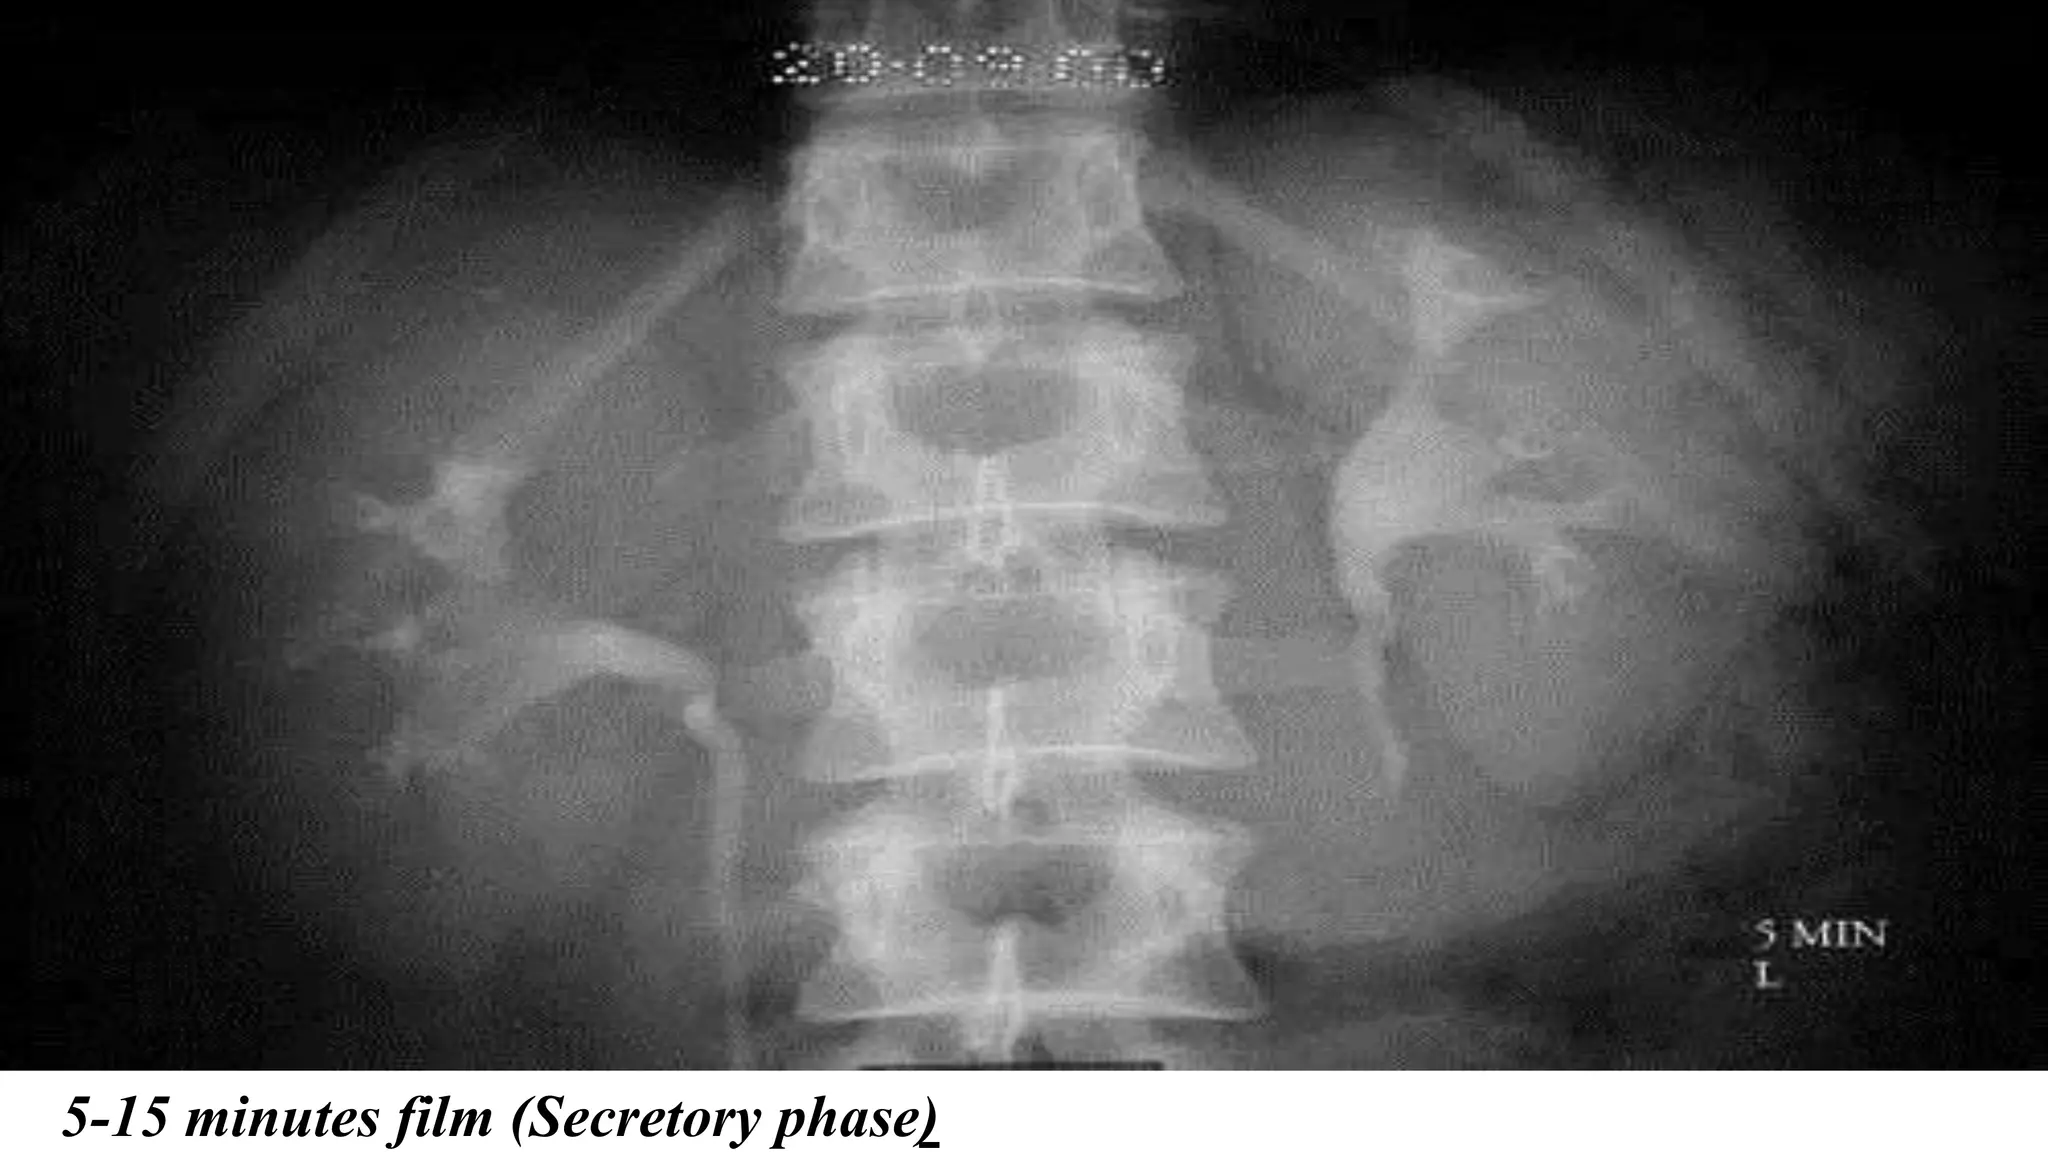

•5-15 minutes film (Secretory phase)

5-15 minutes film (Secretory phase)

•5-15 minutes film(Secretory phase) •-Both Kidney contour •-Contrast is filling both the Pyelum or not, •-is there any delayed filling?

5-15 minutes film(Secretory phase)